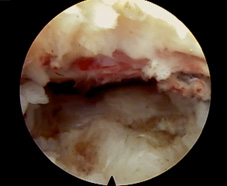

* 經皮內視鏡腰椎間盤突出切除手術:全程使用脊椎內視鏡進行手術,對於骨骼與肌肉組織的破壞比前述手術更少,手術傷口不到一公分,有望在不久的將來成為治療腰椎間盤突出症的主流手術。

經皮內視鏡腰椎間盤突出切除手術